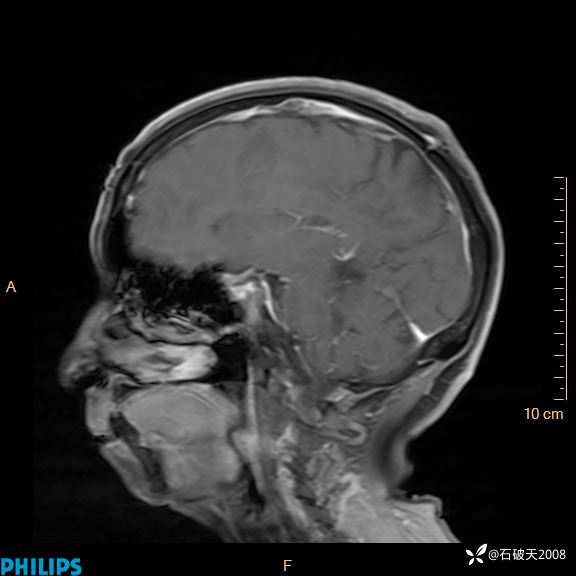

既往史:既往患“脑部占位”病史3年,未定期复查;有高血压病史4年,最高血压达170/115mmHg,间断口服降压药物“硝苯地平缓释片 1片 bid”稳定血压,血压未监测,3年前有“脑梗塞”病史,遗留言语不利;20余年前因“阑尾炎”在XX镇卫生院手术治疗,有先天智力低下,否认外伤史、输血史、献血史以及药物、食物过敏史。预防接种史不详。

增强矢状位